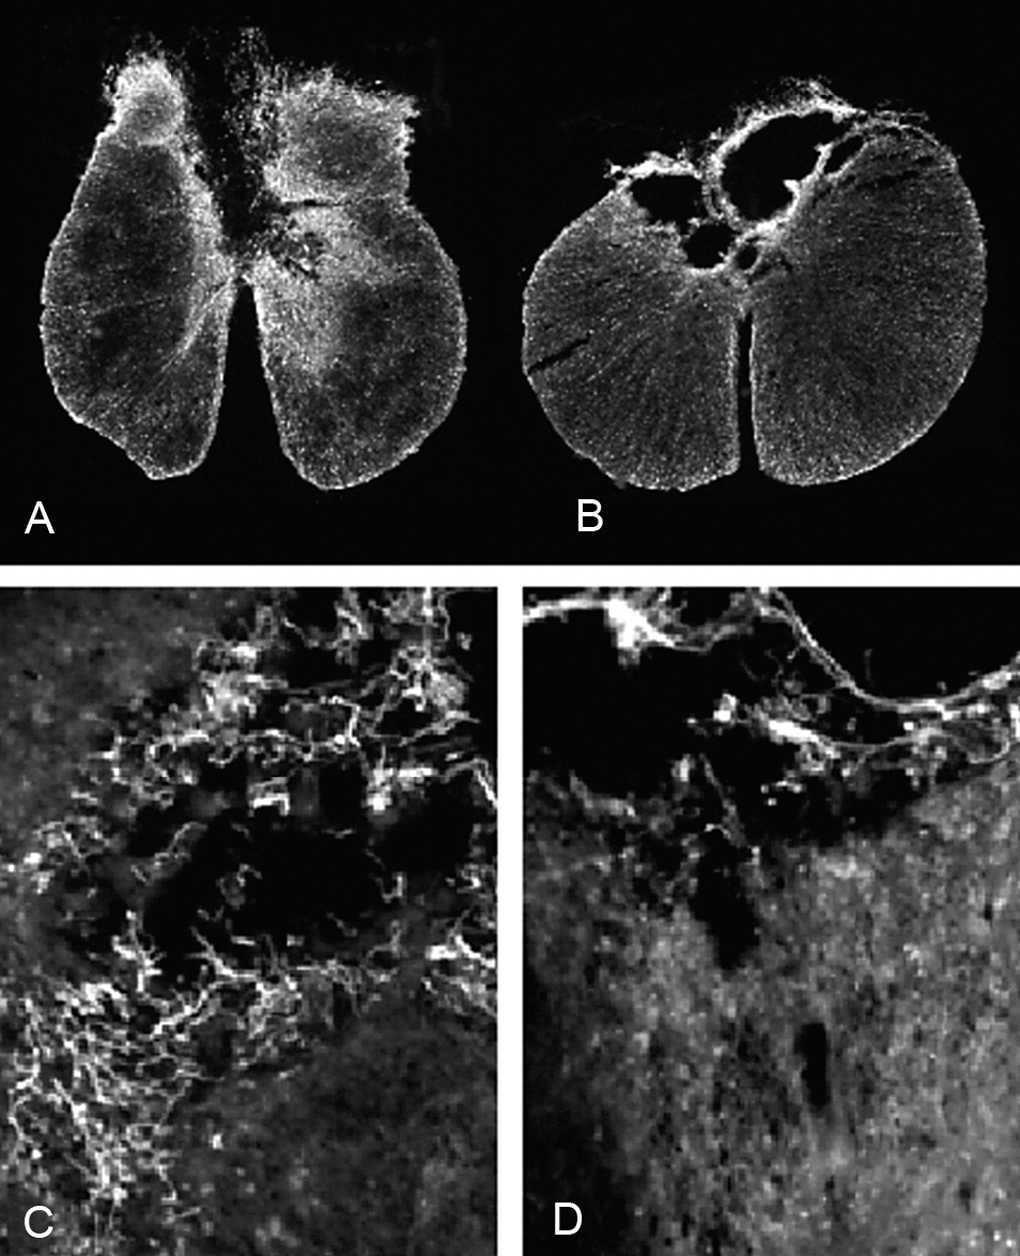

En todos los animales de ambos grupos experimentales la lesión afecta principalmente a la región dorsal de la médula espinal. En los animales del grupo DM, la lesión incluye el funículo dorsal, comprometiendo, en la mayoría de los animales, el tracto córtico-espinal e incluso el canal central. Asimismo, en varios animales de este grupo experimental también se observaron lesionadas las regiones dorsolaterales de la médula espinal. Un patrón similar se encontró en las secciones de los animales del grupo GE, aunque en la mayoría de ellos la lesión se circunscribe casi exclusivamente al funículo dorsal y en alguno se extiende hacia regiones dorso-laterales (figs. 1A-B). El promedio del área de médula espinal preservada fue mayor en el grupo GE que en el DM (3,12 ± 0,07 y 2,85 ± 0,09 mm2, respectivamente), presentando diferencias significativas entre ambos grupos experimentales (p < 0,05). Cualitativamente, se observaron más células positivas para p75 en las secciones medulares de los animales con trasplante de GE que en los animales con inyección de DMEM (figs. 1C-D).

Figura 1. Secciones transversales de la médula espinal inmunomarcadas contra GFAP de las ratas con (A) trasplante de glía envolvente del bulbo olfatorio (x4) y (B) con trasplante de DMEM (x4). Microscopia óptica con epifluorescencia de (C) campos próximos a la zona lesionada (*) de secciones medulares inmunomarcadas para p75 de ratas con trasplante de glía envolvente (x20) y (D) con inyección de DMEM (x20). Todas las manchas blancas y filamentosas de las imágenes C y D corresponden a células inmunorreactivas al p75. Nótese que existen más en la imagen correspondiente al grupo GE que al DM.